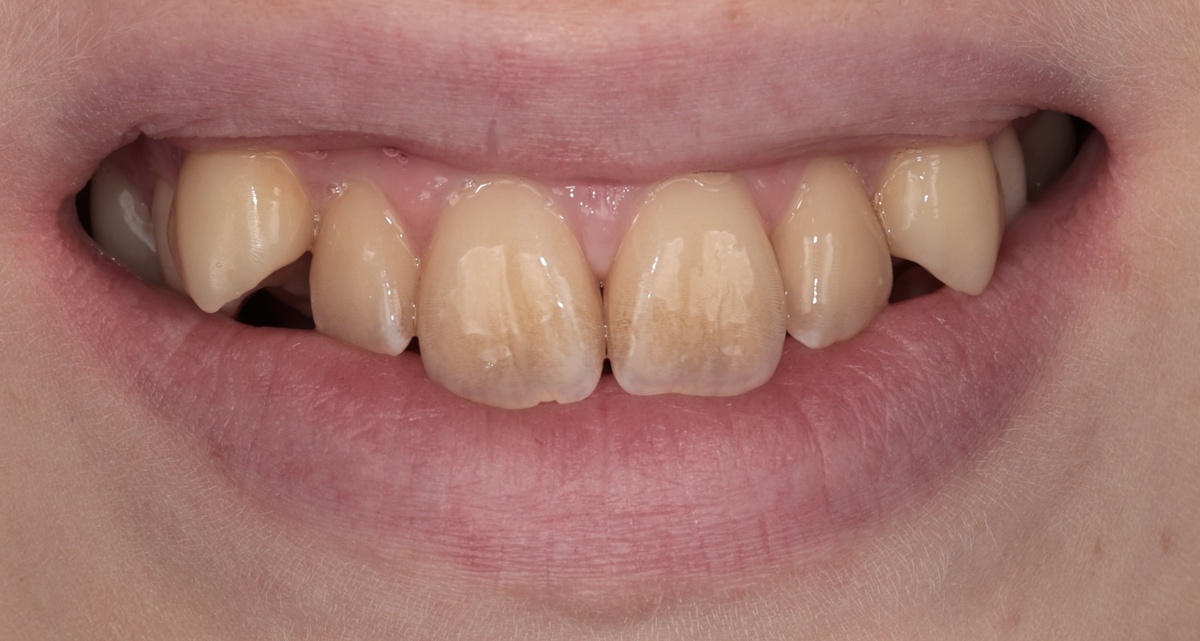

День установки брекет-системы на верхнюю челюсть

Посмотрите на фото "до" и "после 3 месяцев". Разница очевидна даже неспециалисту. Клыки из положения "дракула" перешли в положение "почти нормально".